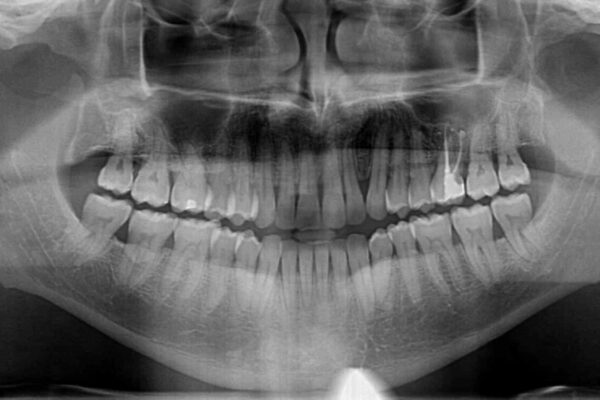

前歯でものを噛みきりたいとのことで来院された患者様です。

以前矯正治療を経験されたそうですが、舌の突出癖により上下前歯に隙間ができている様子でした。

治療前

• 前歯でものを噛みきりたい 目立たない装置でのワイヤー矯正 治療前画像